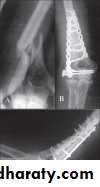

Supracondylar fracture of humerus:

Supracondylar humeral fracture in children is one of the most common fractures seen in the pediatric orthopedic clinic setting worldwide. It's a fracture that occurs at the supracondylar area or the metaphysis of the distal humerus & accounts for 65.4% of upper extremity fractures in children .There are two types of supracondylar fractures in children according to direction of displacement of distal fragment i.e. extension type (97%) and flexion (3%).Immobilisation in an above-elbow backslab in 90 degrees elbow flexion with sling for 3 weeks. The backslab and sling should be worn under clothing (e.g. loose fitting shirt) and not through the sleeve

A gentle reduction can be achieved by an anterior push on the distal fragment as the elbow is flexed to 90 degrees

Requires urgent reduction and percutaneous pin fixation